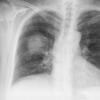

Case 2  Lingular pneum Lat

Date: 04/17/2005

Views: 7024